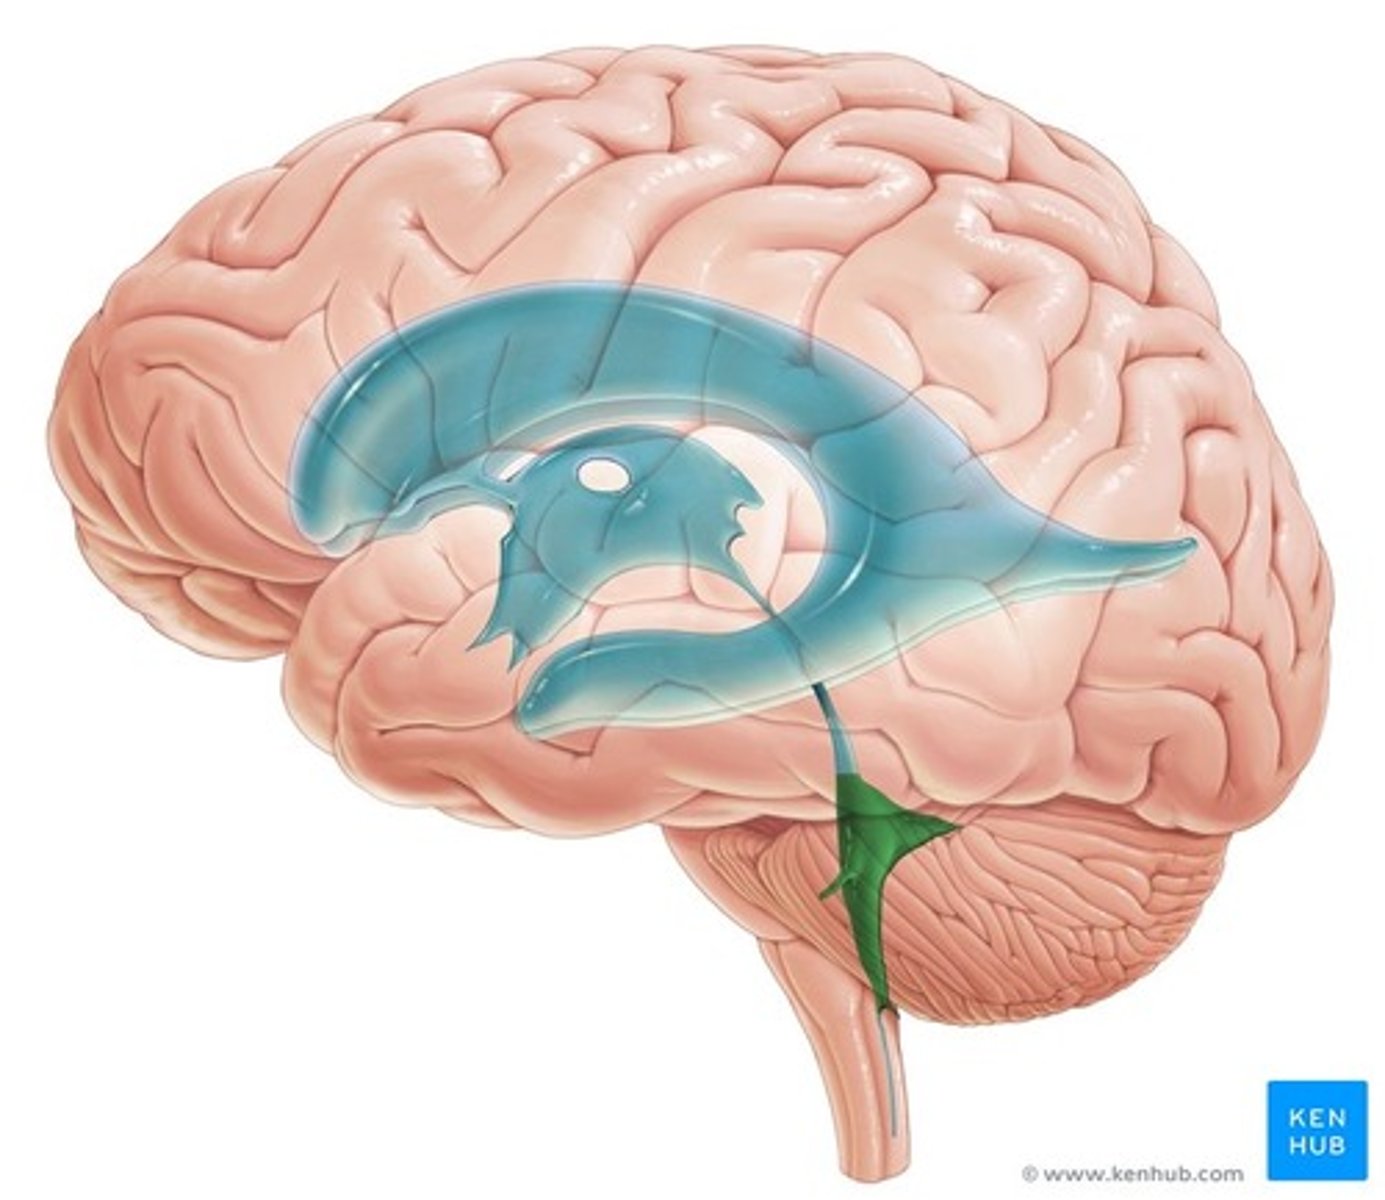

Lateral Ventricle

Third Ventricle

Fourth Ventricle

Cerebral Aqueduct

Sheep Lateral Ventricle

-produces and contains cerebrospinal fluid

Sheep Third Ventricle

sheep 4th ventricle